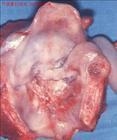

喉癌專題

喉癌的檢查與診斷

喉癌在我國北方比南方發病率高,城市比農村發病率高,男性多于女性。發病年齡多在40—70歲之間。

病因病理